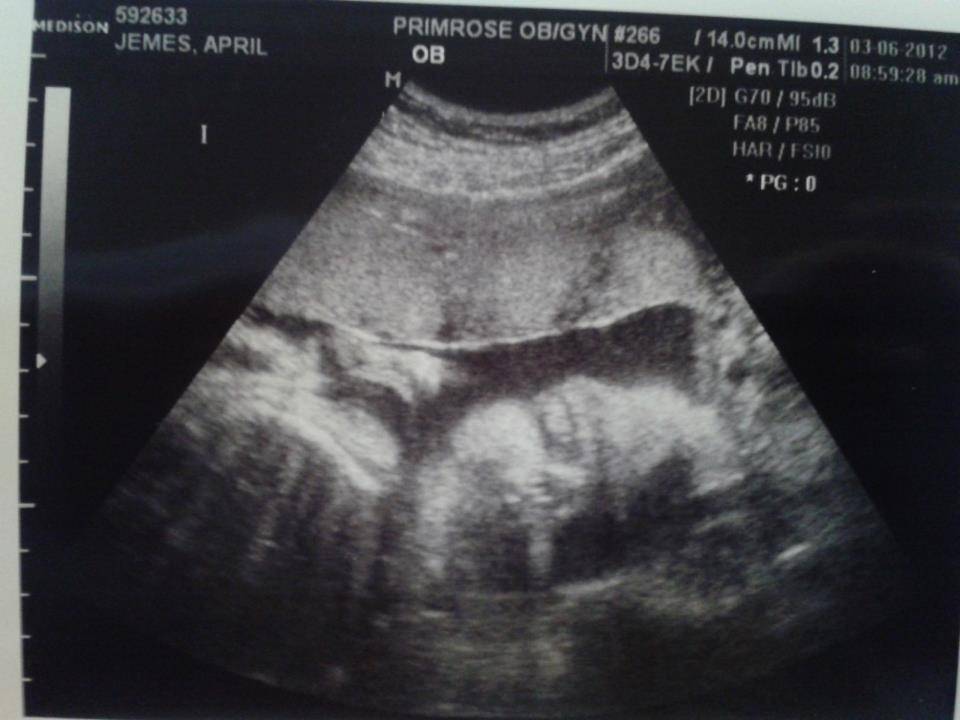

Фото УЗИ на 32 недели беременности

УЗИ плода в 32 недели показывает уровень его развития. Оно позволяет внимательно посмотреть головной мозг, проанализировать мозжечок, полушария, боковые желудочки. Их ширина колеблется около 10 мл. Если данный показатель более средних, то это может свидетельствовать о наличии гидроцефалии. Чаще всего данная патология вызывается давлением, оказываемым околоплодными водами на головку малыша.

Далее смотрят на УЗИ лицо, которое должно включать пропорционально расположенные и сформированные глазницы. Во время проведения исследований на 3д оборудовании могут обнаруживаться патологии, которые незаметны при проведении двухмерного УЗИ. Если диагностику делают на современном оборудовании, то можно рассмотреть грыжи и расщепления позвоночника. Ультразвуковые волны позволяют оценить состояние кожного покрова. Теперь он отличается плотностью, телесным оттенком. Ребеночек словно разглаживается в результате скопления подкожного слоя.